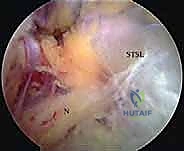

- الشق فوق الكتفي (Suprascapular Notch): هذه هي المحطة الحرجة الأولى. يمر العصب عبر هذا الشق العظمي الضيق الموجود في الحافة العلوية للوح الكتف. يُغطى هذا الشق بشريط ليفي قوي يُسمى الرباط المستعرض الكتفي (Transverse Scapular Ligament - TSL). يمر العصب تحت هذا الرباط، بينما يمر الشريان والوريد فوق الكتفي فوق الرباط. هذه المنطقة هي الموقع الأكثر شيوعًا للانضغاط.

- الشق الشوكي الحقاني (Spinoglenoid Notch): يواصل العصب رحلته ليلتف حول القاعدة الجانبية لشوكة لوح الكتف (Spine of the scapula) عبر ممر ضيق آخر يُعرف بالشق الشوكي الحقاني. هذه هي المحطة الحرجة الثانية للانضغاط. يُغطى هذا الشق أحيانًا برباط يُسمى الرباط الشوكي الحقاني (Spinoglenoid Ligament).

- الكيسات العقدية المجاورة للشفا (Paralabral Ganglion Cysts): تُعد هذه الكيسات من أهم وأشهر أسباب انضغاط العصب، خاصة عند الشق الشوكي الحقاني. تنشأ هذه الكيسات عادةً نتيجة تمزقات في الشفا الغضروفي (Labral Tears) لمفصل الكتف (مثل تمزقات SLAP أو تمزقات الشفا الخلفية). يعمل التمزق كصمام أحادي الاتجاه؛ يسمح للسائل الزليلي بالخروج من المفصل وتجمعه لتكوين كيسة، ولكنه يمنع عودته. مع مرور الوقت، تكبر الكيسة وتضغط بقوة على العصب.